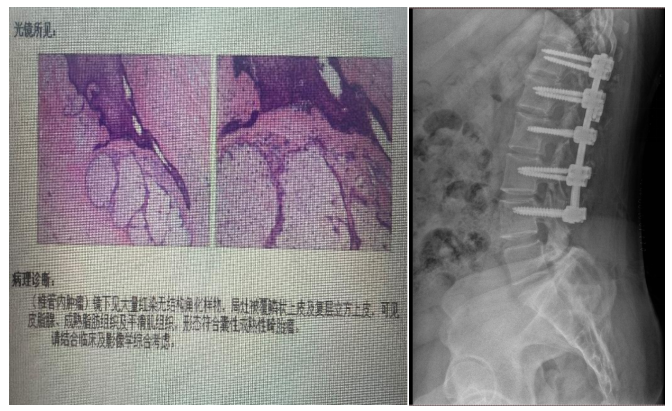

病例3:女性,31岁

患者以“腰部疼痛半月,加重3天”为主诉入院,自诉腰部疼痛,休息后无缓解。专科查体:腰部压痛及叩击痛+,双下肢小腿肌群肌力Ⅳ级+,感觉正常,无明显病理征。

结合患者影像学资料,女性,髓外硬膜下病变,病变位于胸腰段,节段较长,位于圆锥附近,T1、T2混杂信号,并合并有脂肪信号,患者症状较轻,病情发展时间较长,倾向于畸胎瘤可能。

行“胸腰椎椎管内肿瘤切除+钉棒内固定术”,术后腰部疼痛症状明显缓解,下肢肌力恢复正常。